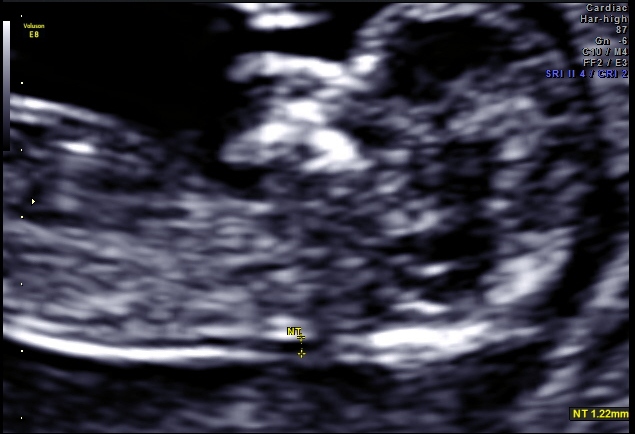

Well this little one has a very boy-ish head but I'm not sure what to make of the nub, if that's vene a nub captured in the images. Any guesses would be much appreciated.

Pic 1 makes me think boy but Pic 2 looks pretty girly so I am saying 60/40 girl lean.

In the second pic I think the nub looks girly, so I would lean pink. I wouldn't focus too much on skull shape because the head is a bit distorted in these images and also looks like head is turned sideways.

I think girl nubs look slightly turned up when baby is slightly tilted....to me it appeared girl more than boy!!! Many congrats!!!!